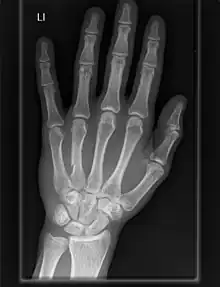

The carpometacarpal (CMC) joints are five joints in the wrist that articulate the distal row of carpal bones and the proximal bases of the five metacarpal bones.

Fingers

- The second metacarpal articulates primarily with the trapezoid and secondarily with the trapezium and capitate.

- The third metacarpal articulates primarily with the capitate,

- The fourth metacarpal articulates with the capitate and hamate.

- The fifth metacarpal articulates with the hamate.

Osteoarthritis of the carpometacarpal joints is a type of joint disease that results from breakdown of joint cartilage and underlying bone.[13] When it affects the thumb it is termed trapeziometacarpal osteoarthritis.

Carpometacarpal bossing is the presence of a small immovable protuberance over the joint.[14]